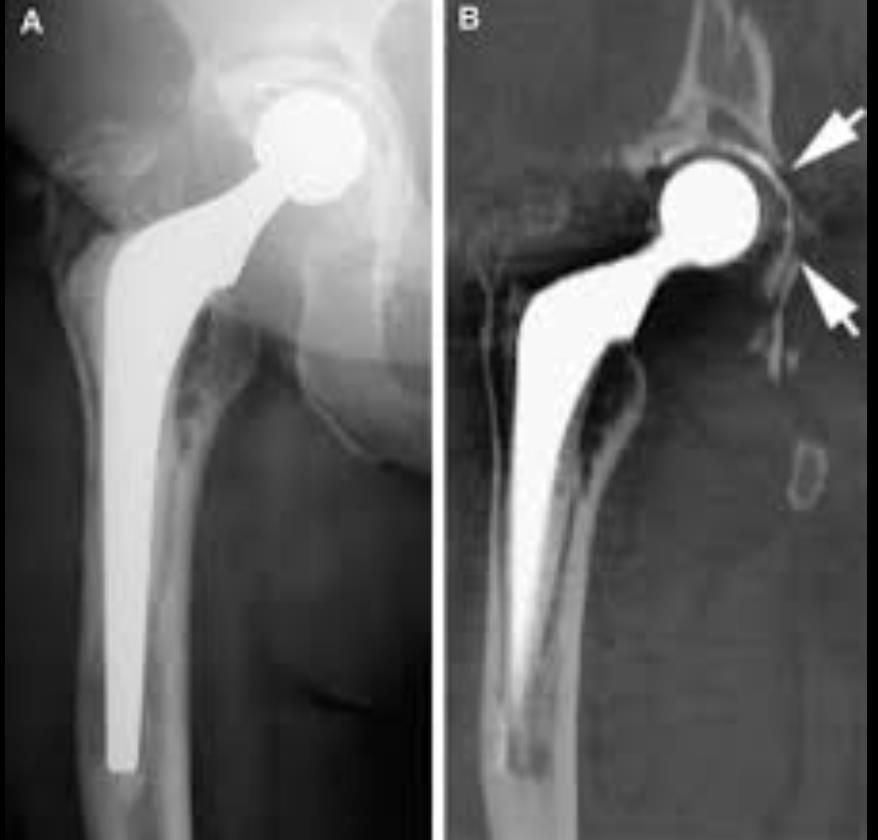

• Imaging

• Plain radiographs to monitor for progression

• underestimates lesion size and may miss small lesions

• Computed Tomography

• creates true 3D rendering of components, allowing for monitoring of osteolytic defect progression

• useful for surgical planning

• helpful with determining component positioning

• possible future utility in establishing the degree of linear and volumetric wear